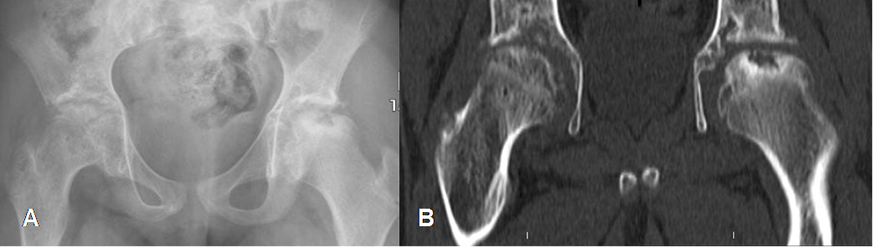

Fig 79. Osteonecrosis bilateral.

A: Rx AP y B: TAC reconstrucción coronal. Osteonecrosis bilateral de caderas, en una niña con anemia drepanocítica.